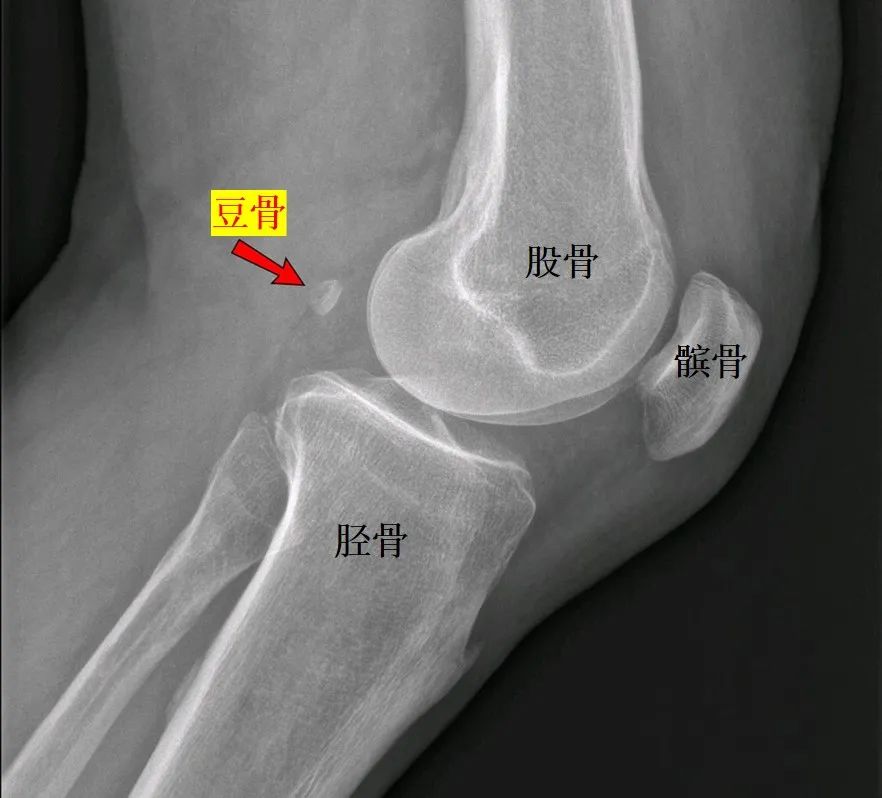

此外,在膝盖后外方,有些人在腓肠肌(小腿肌)上端的筋腱内还埋有一个籽骨,叫做豆骨(fabella)。 近年来,具有豆骨的人数在增加。例如英国科学家分析了过去的100多年间人群中具有豆骨人的比例,共58篇研究报告,涵盖27个国家,21676个膝盖,发现在1918年时,具有豆骨的人比例只有11.2%,而在2018年这个比例就已经增加到39%。

豆骨的位置 图片来源:wikimedia,经作者修改